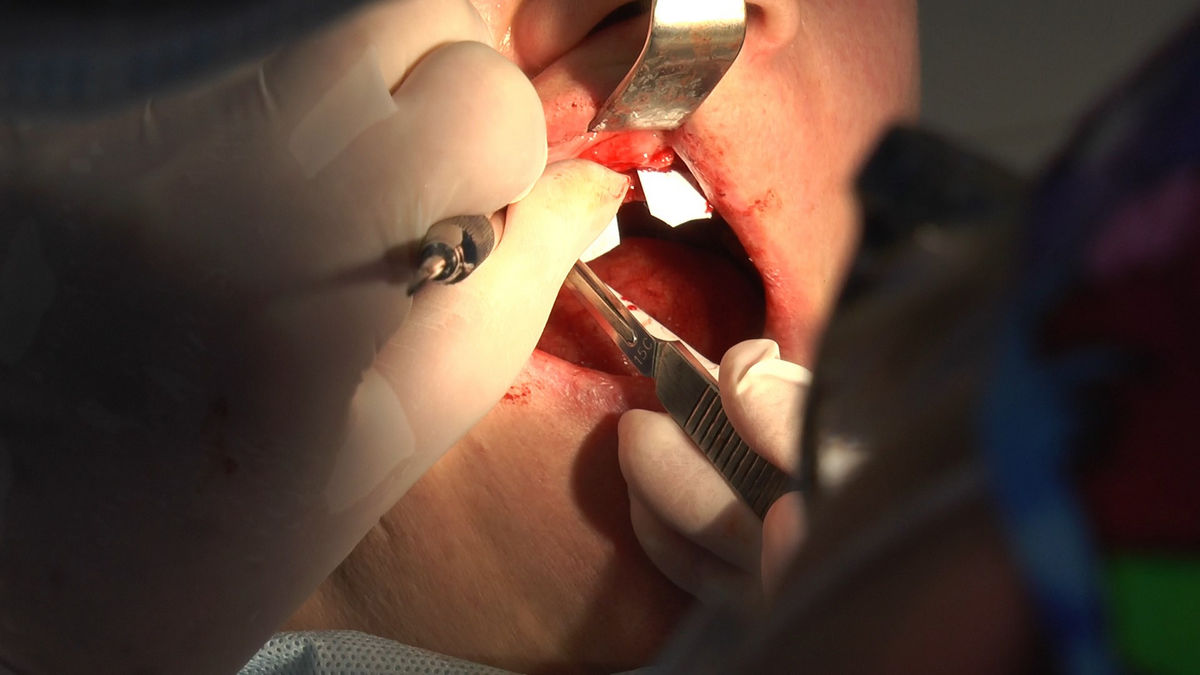

Practiculum Implantologii – Sezon V/B, sesja 8, część 4